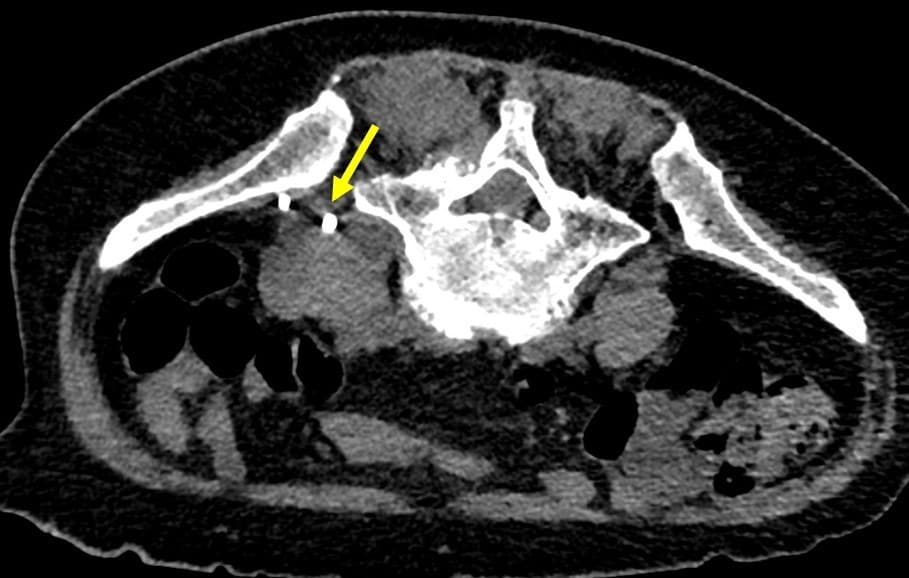

乳癌術後の再発・転移の検索目的で行われた単純CTで左腸腰筋膿瘍が疑われた。当科にCTガイド下ドレナージによる治療が依頼された。造影CTにて膿瘍は左大腰筋から左脊柱起立筋や左腰方形筋にかけて広範囲に認められた。形状は不整形で分葉状であり、辺縁に造影効果が認められ、内部は液体濃度の低吸収であり、隔壁も認められた。CTガイド下にドレナージカテーテルが膿瘍内に留置された。乳白色の膿汁がドレナージでき、ドレナージ後のCTでは膿瘍の縮小を認めた。

腸腰筋膿瘍の症状として、発熱、腰痛、psoas positionの三主徴が知られているが、実際に全てが揃う頻度は高くない。単純CTでは診断が困難な場合もあり、熱源不明で発見が遅れることもある。造影CTでは膿瘍が検出しやすくなり、さらにドレナージを行う上でも膿瘍腔の形状や範囲が確認できるため、非常に有用である。

椎体、椎間板、結腸、虫垂、小腸、腎尿路系、膵などの隣接臓器からの炎症の波及による続発性の腸腰筋膿瘍の場合が多いため、膿瘍形成の原因検索においても造影CTは有用であると考えられる。